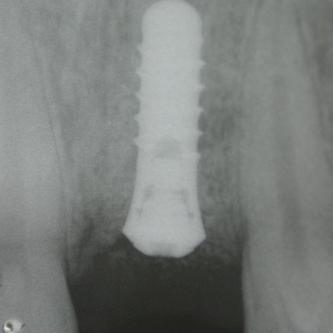

Exemple 14: 6 mois plus tard, l'implant est introduit dans cette greffe sans toucher le sinus.